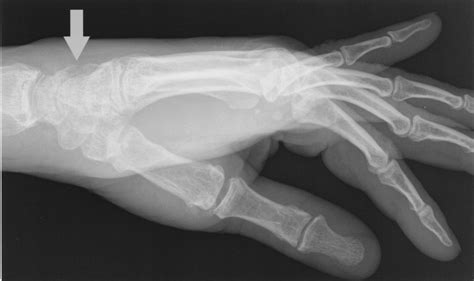

Diagnosing a fractured triquetral bone involves a combination of physical examination and imaging tests. The diagnostic process typically includes:

• Physical examination: A healthcare provider will assess the wrist for swelling, tenderness, and range of motion.

• X-rays: Standard X-rays can often reveal a fracture in the triquetral bone. However, due to the small size of the bone, additional views or specialized imaging may be required.

• CT scan: A computed tomography (CT) scan provides detailed images of the bone and can help identify fractures that are not visible on standard X-rays.

• MRI: Magnetic resonance imaging (MRI) can be used to assess soft tissue injuries and provide a more comprehensive view of the wrist joint.

In some cases, a combination of these imaging tests may be necessary to confirm the diagnosis and determine the extent of the injury.